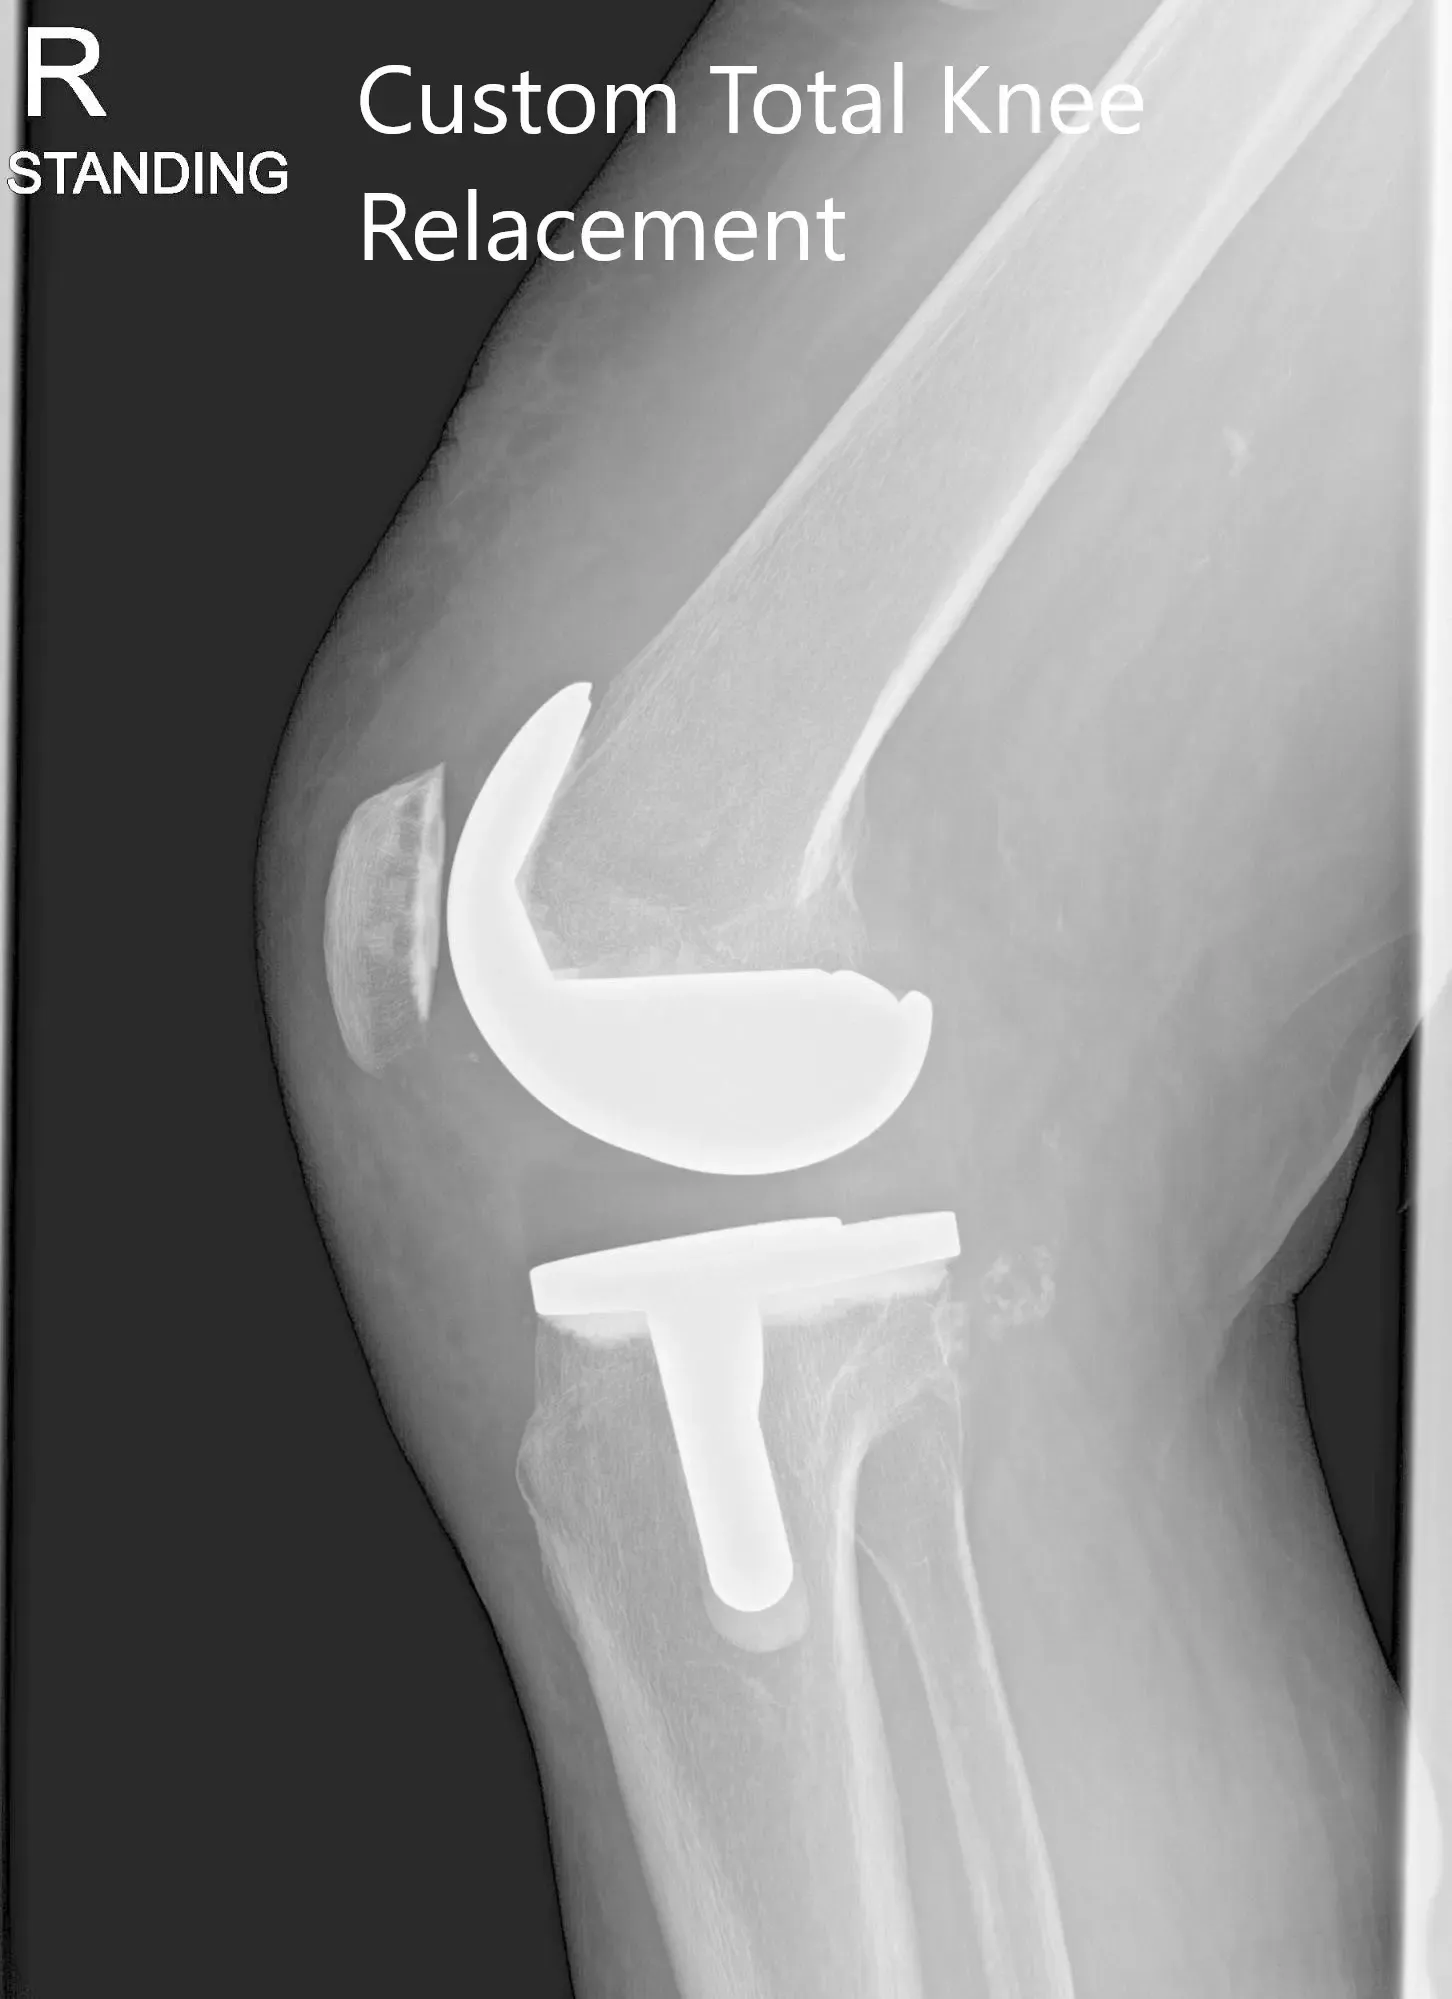

Post Operative X-ray of the patient’s right knee showing AP and Lateral Views

The patient underwent Right Total Knee arthroplasty using custom total posterior stabilized knee with 14mm posterior stabilized polyethylene implant with custom tibial tray and patellar component.

The patient was able to walk the same day after surgery and reported an excellent range of motion of the knee in the subsequent visits. She was able to drive and continue his daily activities such as walking, climbing stairs pain-free after a period of physical therapy. In the following subsequent post-operative visits, she reported no stiffness in the right knee with an excellent range of motion. The patient had excellent recovery from left knee arthritis pain due to offloading of weight from successful right total knee arthroplasty.